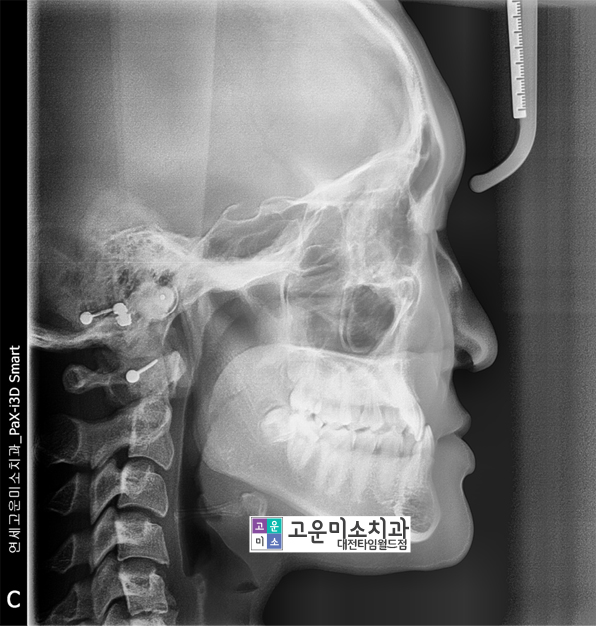

옆에서 찍은 엑스레이를 보면

아랫니가 윗니를 거꾸로 무는

정도가 심한 것을 알 수 있습니다.